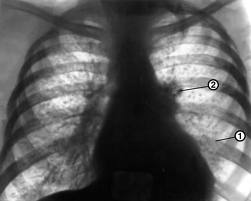

Чаще всего туберкулез поражает органы дыхания. Люди с очень низким иммунным статусом (больные ВИЧ-инфекцией) могут страдать от "атипичного" или "внелегочного" туберкулеза, который развивается, когда бактерия распространяется из легких в другие органы. Туберкулез может поражать лимфоузлы, костную ткань, в том числе позвоночник, ткани, окружающие сердце (перикард), плевру, органы пищеварительной системы, почки и мочеиспускательный канал. Иногда туберкулез вызывает воспаление головного мозга (менингит) или спинного мозга. К симптомам менингита относятся: раздражительность, бессонница, усиливающиеся головные боли, спутанность сознания, потеря сознания и судороги. Такие симптомы как лихорадка, сильная хроническая усталость и резкая потеря веса являются "универсальными" для всех форм туберкулеза.

В начальной стадии ВИЧ: проводится изучение жалоб и анамнеза пациента, объективное обследование, анализы крови и мочи, рентгенография органов грудной клетки, микроскопическое исследование и посев мокроты на питательные среды, оценка внутрикожной реакции Манту. С учетом высокой частоты внелегочных поражений у ВИЧ-инфицированных больных туберкулезом, немаловажная роль в диагностике отводится биопсии лимфатических узлов, селезенки, печени, костного мозга и других органов. Проводится компьютерная томография. В качестве дополнительного исследования рекомендуется использование метода иммуноферментного анализа (ИФА) для выявления противотуберкулезных антител и антигенов.